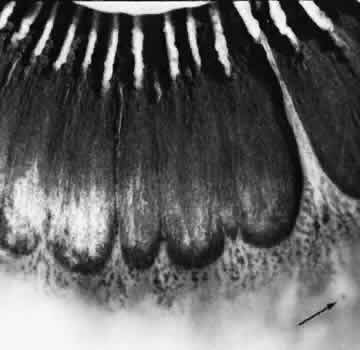

Retinoschisis associated with a bullous architecture and prominent reticular cystoid degeneration has been termed reticular degenerative retinoschisis. Reticular degenerative retinoschisis can be distinguished from typical degenerative retinoschisis by the large extent of retinal involvement, a round or ovoid configuration with bullous elevation of the extremely thin inner layer, and an irregular, pitted outer layer (Figs. 20 and 21). Typical cystoid degeneration is always present anterior to the schisis; reticular cystoid degeneration is usually prominent at some site in the involved eye. Blood vessels coursing through the inner layer give it an arborizing reticular pattern on contact lens biomicroscopy. The intraretinal cavity is optically empty; the outer wall is irregularly excavated to produce a pocked or honeycomb appearance. Round or ovoid holes are often present in the outer retinal layer; they are single or multiple, frequently large, and usually associated with a rolled posterior edge.13

Microscopic sections demonstrate the extremely attenuated, blood vessel-containing inner layer composed of the internal limiting membrane and remnants of the nerve fiber layer (Fig. 22). The honeycomb appearance of the outer layer corresponds to irregular excavations. In some areas, the outer layer is made up of outer plexiform, outer nuclear, external limiting, and rod and cone layers; in other areas it is reduced to only the external limiting and the rod and cone layers; round or ovoid holes may be present (Fig. 23).

Fig. 22. Reticular degenerative retinoschisis. Note complete loss of radial supporting columns of retina and marked elevation of delicate inner wall, which contains fine blood vessels. Outer wall shows periodic exaggerated thinning. (Hematoxylin-eosin; × 60.)

Fig. 23. Reticular degenerative retinoschisis with hole in outer wall and localized retinal detachment. Margins of hole are rolled and covered by a garland of degenerating photoreceptor outer segments. (Hematoxylin-eosin; × 250.)

Reticular degenerative retinoschisis is evident in 1.6% of adult patients, is bilateral in only 16% of these, and thus is noted in 0.95% of adult eyes (see Table 3). The lesion is found most commonly in the inferior temporal quadrant. A band of typical cystoid degeneration always separates the schisis from the ora serrata; the schists usually reaches the equator and often extends appreciably into the posterior retina.

On contact lens biomicroscopy, many retinal blood vessels present irregular contours, telangiectases, occluded segments, and microaneurysms. Between these vessels, the inner wall has a finely textured appearance and variable white, glistening particles on the vitreous side. The outer retinal wall is best seen when scleral depression produces a “white with pressure” phenomenon and reveals the honeycomb appearance. The retinal pigment epithelium often has a granular, salt-and-pepper appearance, and outer-layer retinal breaks are common. These breaks are particularly likely near the anterior and posterior margins of the schisis.